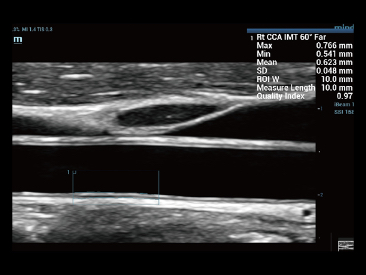

Desde que se fund├│ la compa?├Ła, Mindray ha explorado incansablemente nuevas formas de mejorar la confiabilidad del diagn├│stico. Con la revolucionaria tecnolog├Ła de ZONE Sonography?, la nueva plataforma ZST+ de Resona?7 lleva la calidad de la imagen por ecograf├Ła a un nivel superior mediante el procesamiento de datos de canal y la adquisici├│n de zona.

Adem├Īs de la calidad de imagen de primer nivel, Resona?7 tambi├®n mejora las capacidades de investigaci├│n cl├Łnica con el revolucionario V?Flow para la evaluaci├│n hemodin├Īmica vascular y con la adquisici├│n de planos m├Īs inteligente a partir de conjuntos de datos 3D para el diagn├│stico del SNC fetal. Al combinar el funcionamiento multit├Īctil basado en gestos m├Īs intuitivo y todas las caracter├Łsticas cl├Łnicas esenciales, Resona?7 realmente lidera las novedades en innovaci├│n de ecograf├Łas.